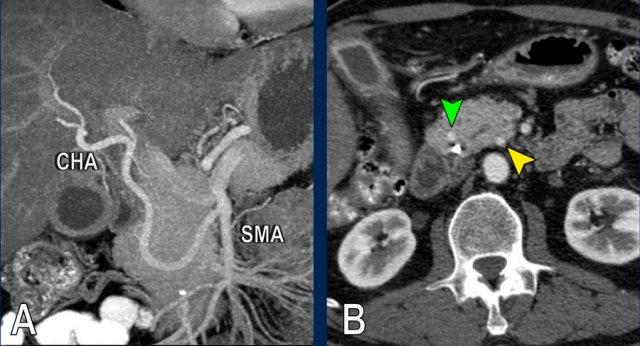

Hình CT axial cho thấy một động mạch gan phải phụ thêm (mũi tên vàng) đi qua vùng lân cận một khối giảm tỷ trọng ở đầu tụy (đầu mũi tên).

Sự liên quan mạch máu được đánh giá rõ hơn trên ảnh tái tạo mặt phẳng đứng dọc. Có sự áp sát 90 – 180° của động mạch gan phải thay thế (mũi tên trắng) bởi ung thư biểu mô tuyến đầu tụy (đầu mũi tên trắng).

Động mạch gan trái nguyên bản đi theo hướng ra trước hơn, tĩnh mạch cửa nằm ở giữa.

Cuộc phẫu thuật là cắt bỏ diện R1.

Các hình ảnh axial của cùng bệnh nhân có chú thích.

Hình MIP mặt phẳng đứng ngang này cho thấy một động mạch gan phải thay thế xuất phát từ phía phải của SMA (mũi tên vàng trong A).

Động mạch này đi qua vùng lân cận đầu tụy.

Hình CT axial cho thấy đường đi của động mạch gan phải thay thế phía sau tĩnh mạch cửa (đầu mũi tên vàng) và động mạch gan trái nguyên bản đi phía trước tĩnh mạch cửa (đầu mũi tên xanh lá).

Đây là phát hiện tình cờ ở một bệnh nhân không có bệnh lý tụy.

Các hình ảnh mặt phẳng đứng ngang của một bệnh nhân có khối u ở đầu tụy và động mạch gan phải phụ thêm.

Lưu ý sự áp sát của động mạch phụ thêm bởi khối u.

Các hình ảnh cho thấy một biến thể giải phẫu trong đó động mạch gan chung xuất phát hoàn toàn từ SMA.

Động mạch gan được thấy đi trong nhu mô đầu tụy (mũi tên vàng và xanh lá trong B).